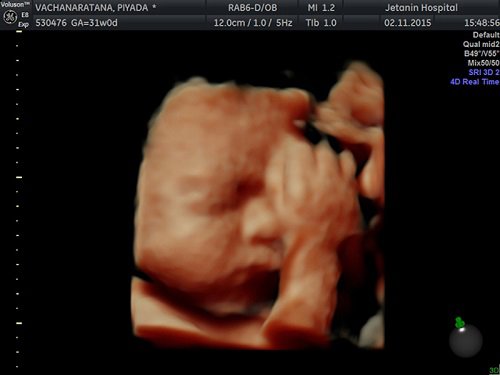

Siêu âm 4 chiều vào thời điểm nào thích hợp nhất?

Siêu âm thai là việc làm quan trọng trong thai kỳ, không chỉ giúp mẹ nhìn thấy hình ảnh của con mà còn theo dõi được sự phát triển của bé yêu qua từng thời kỳ. Ngày nay, Y học ngày càng phát triển, kỹ thuật siêu âm tiên tiến hơn, siêu âm 4 chiều được mọi người sử dụng nhiều nhất.